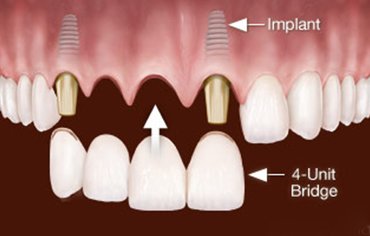

In case of more missing teeth, multiple implants are placed and they are joined by IMPLANT PROSTHESIS.

After clinical examination and radiographic assessment[ CBCT, OPG], a small opening is made in the gums to expose the bone. Surgical guides are prepared and implant made up of TITANIUM is placed. Once the IMPLANT is placed, bone is deposited and the implant unites with the bone. After placing the implant perfectly, ABUTMENT is placed . Abutment is a post that connects implant to the prostetic tooth. After 2-3 weeks artificial tooth is placed.